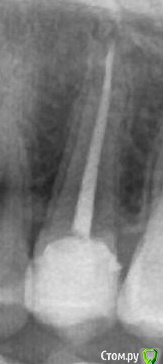

IvanStepanovich Опубликовано 23 марта, 2017 Поделиться Опубликовано 23 марта, 2017 Добрый день, имеется зуб – депульпированный второй премоляр слева сверху. После лечения каналов зуб был обточен под эндокоронку Cerec Empress. В настоящий момент жалоб и болей нет, зуб никак не беспокоит. Но эту конструкцию хочу заменить т.к. не нравится шероховатость жевательной поверхности и форма реставрации.Будет ли установка новой эндокоронки наиболее адекватным средством восстановлением моего зуба? Или же в моем случае коронка (с культевой вкладкой или композитом) будет лучшим решением? Спасибо. Ссылка на комментарий

IvanStepanovich Опубликовано 23 марта, 2017 Автор Поделиться Опубликовано 23 марта, 2017 Зуб был пролечен и восстановлен в январе 16г, сразу после фиксации все было ОК, не было никаких шероховатостей. Через пару недель в этом зубе появилась боль (тупого характера, ближе к корню, боль лишь при накусывании), доктор сказал, что вкладка возможно чуть завышает прикус и подпилил ее прямо во рту (между снятием слепка и фиксацией вкладки были заменены 2 реставрации - одна на 2 моляре справа снизу, вторая на 1 моляре слева сверху). Сразу после первого подпиливания (начало-середина февраля 2016) боль в зубе утихла, однако временами все же была (боль тупого, ноющего характера в районе корня зуба, эпизодически при жевании), где-то в апреле-мае 2016 тот же доктор вновь мне подпилил эту вкладку, с тех пор зуб не беспокоит никак. Делали снимок в конце 2016г, по словам врача (он же лечил каналы и подпиливал эту вкладку) с каналом зуба все хорошо, и что вроде как все предыдущие боли были вызваны перегрузкой зуба из-за того, что вкладка завышала прикус. Сейчас кроме собственно формы и шероховатости жалоб нет. Ссылка на комментарий